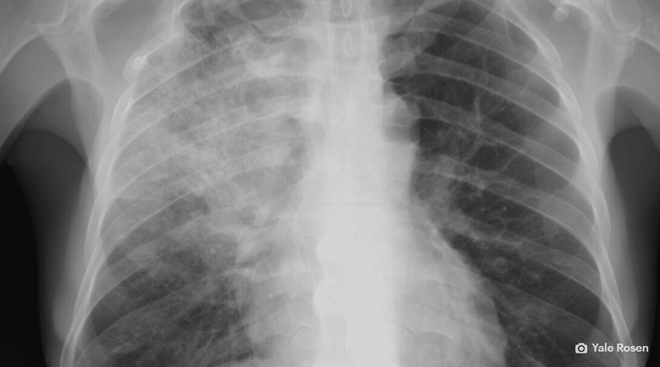

Chụp X-quang có thể tiết lộ những tổn thương kinh hoàng mà virus corona gây ra với phổi.

Những hình ảnh được công bố bởi Hiệp hội X-quang Bắc Mỹ cho thấy chủng virus mới này lấp đầy phổi người bệnh bằng chất nhầy đặc dính, khiến họ khó thở vì không còn không gian trống để đưa không khí vào trong.

Những hiệu ứng này là cơ sở để hàng loạt các công ty công nghệ tung ra những hệ thống trí tuệ nhân tạo (AI) có khả năng phát hiện dấu hiệu lây nhiễm trong phổi.

Khả năng này của AI được lý giải một cách đơn giản: AI, mà cụ thể là thuật toán học sâu (deep learning), có thế mạnh trong việc phân loại hình ảnh. Nếu nó có thể lọc ra những chi tiết từ các bức ảnh độ phân giải cao, nó cũng có thể phát hiện những triệu chứng của virus corona trong các ảnh X-quang và các bản chụp CT.

Hầu hết các hình ảnh dùng để huấn luyện các hệ thống AI đều là ảnh chụp giai đoạn lây nhiễm nặng, có nghĩa là AI sẽ kém hiệu quả hơn trong việc phát hiện những dấu hiệu ban đầu của virus. Chúng còn có thể gặp khó khăn khi phân biệt giữa virus corona với các vấn đề sức khỏe khác có biểu hiện triệu chứng tương tự trong ảnh.